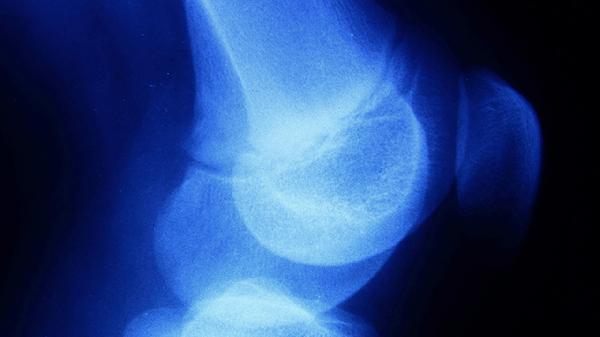

手臂骨膜炎的症状主要有局部疼痛、皮肤红肿、关节活动受限、肌肉无力、发热等。手臂骨膜炎通常由外伤、感染、过度劳损等因素引起,可能伴随局部压痛、皮肤温度升高等表现。

手臂骨膜炎患者常出现持续性或间歇性疼痛,疼痛程度与炎症严重程度相关。早期可能表现为轻微钝痛,随着病情进展可发展为剧烈刺痛。疼痛在活动或按压患处时加重,休息后可能缓解。这种疼痛通常集中在骨膜覆盖的骨骼区域,如前臂尺骨或桡骨部位。

炎症反应会导致患处血管扩张,表现为局部皮肤发红、肿胀。红肿范围通常与炎症范围一致,可能伴随皮肤紧绷感。在细菌感染引起的骨膜炎中,红肿可能快速扩散,皮肤表面可能出现发热。慢性骨膜炎患者的红肿可能呈现暗红色,肿胀程度相对较轻。